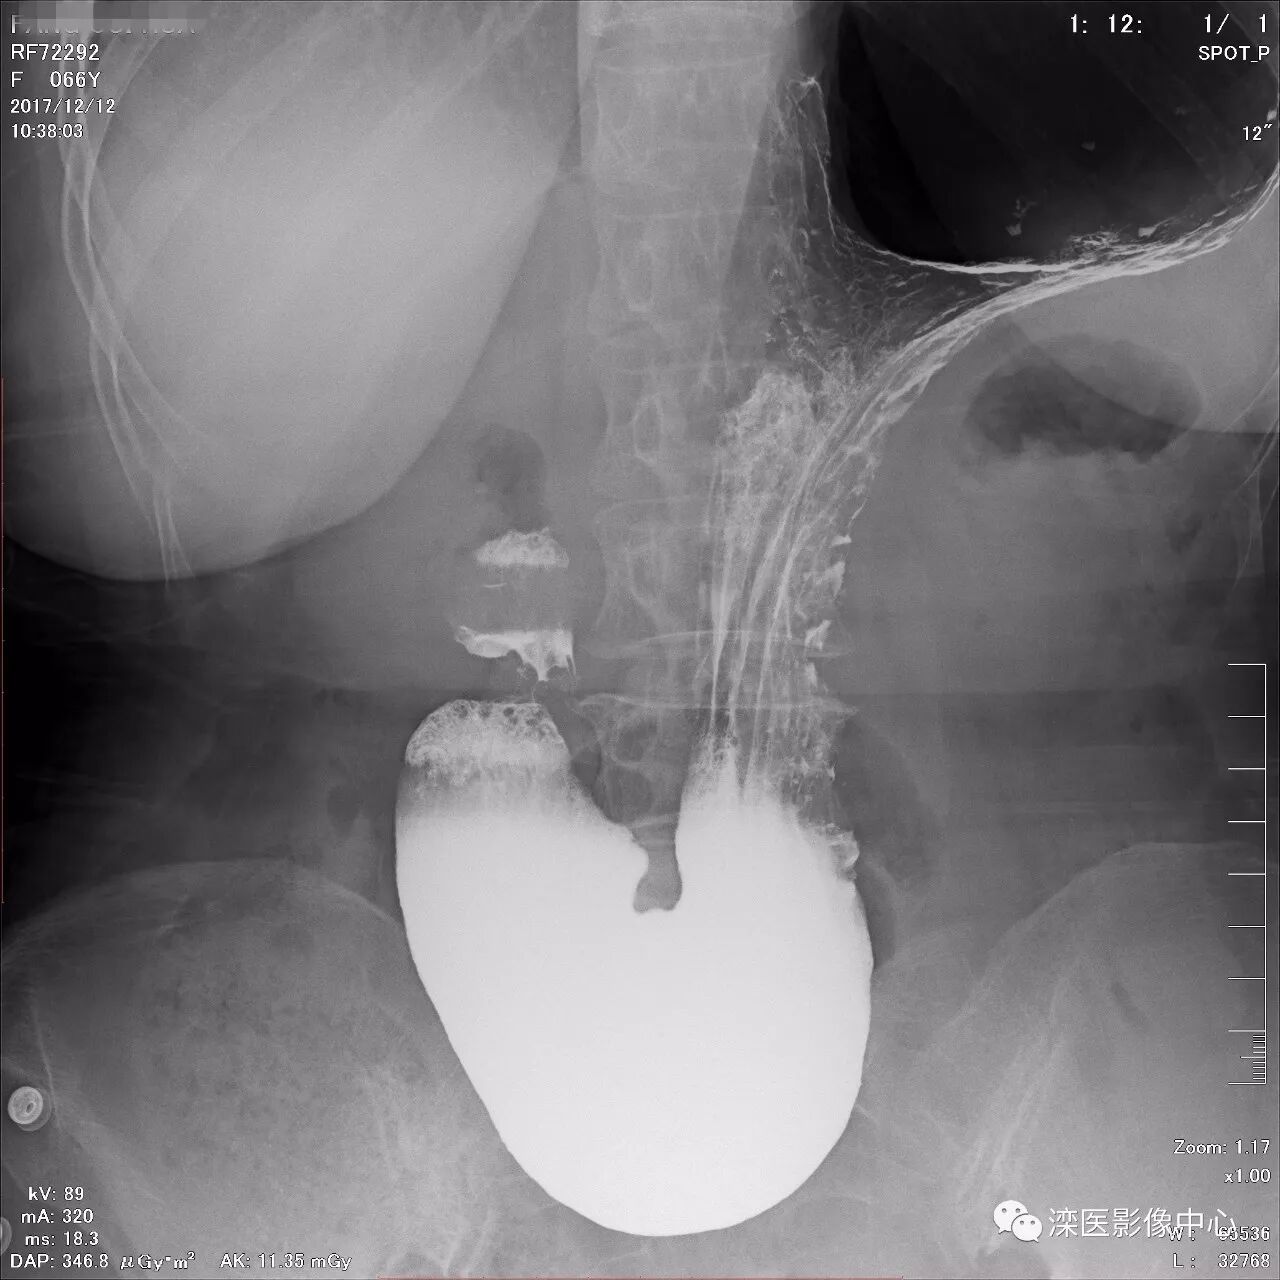

正位,显示食管、贲门及喉咽部的粘膜像)

(左前斜位,显示食管、贲门的粘膜像

(右前斜位,显示食管、贲门的粘膜像)

(以上图像是患者立位+卧位,通过变换体位,多角度显示了贲门胃底、胃体、胃大弯、胃小弯、胃窦、幽门及十二指肠球部、降部、水平部、升部的粘膜像和充盈像。本例患者女性,66岁,此次检查可以清晰显示胃小区结构,检查中发现患有慢性胃炎、胃下垂、十二指肠降部憩室)